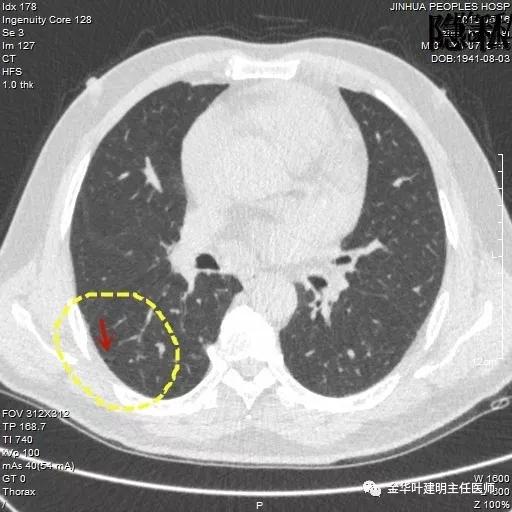

以上是2016年5月的片子,此处有非常小而淡的空腔性病灶,边缘略显磨玻璃,但仍说不上肯定的恶性。